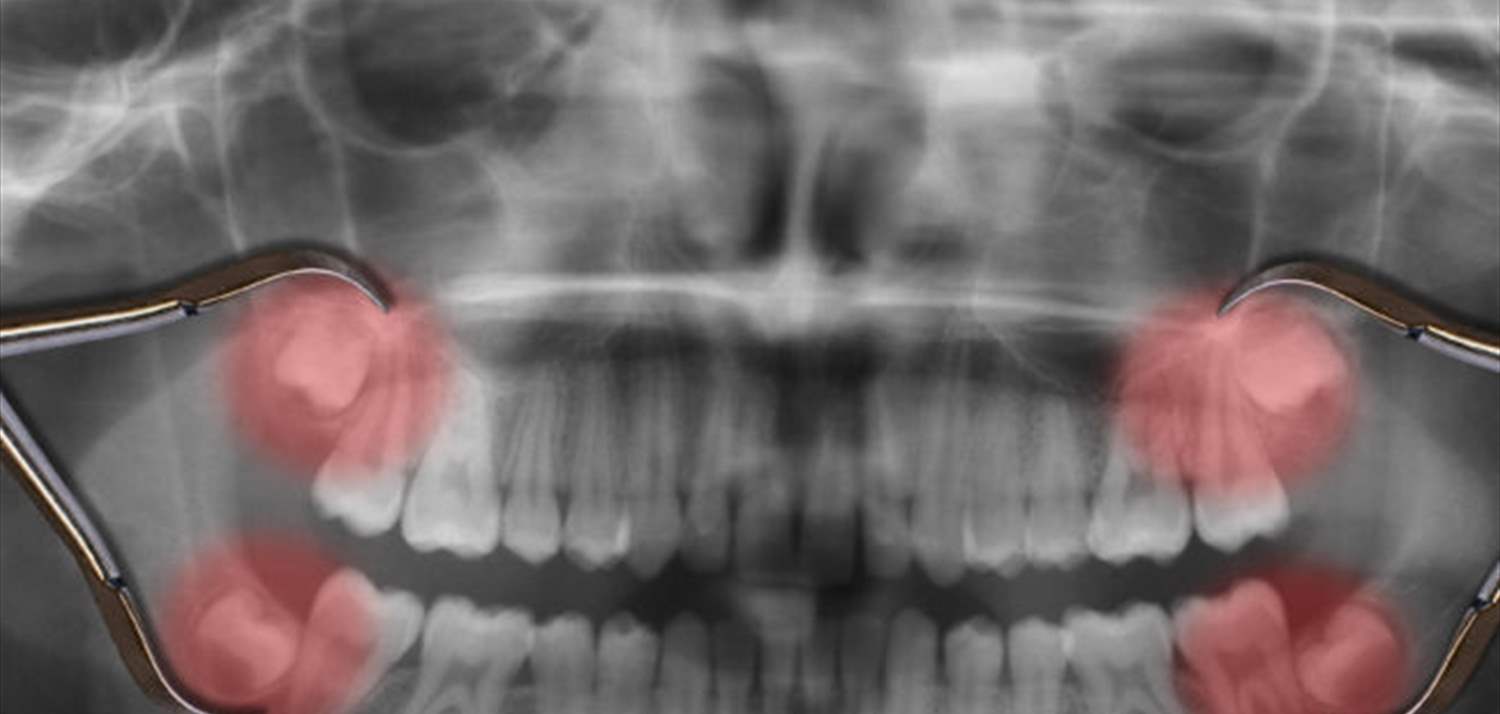

يعاني الكثيرون من آلام ظهور ضرس العقل في أواخر سن المراهقة أو أوائل العشرينات من العمر، حيث يقوم الأغلب باقتلاع الضرس لدى طبيب الأسنان، لكن لماذا يظهر هذا الضرس في سن متأخرة بشكل مخالف لباقي أسنان الإنسان الدائمة؟

بحسب الدراسة المنشورة في مجلة “Science Advances” العلمية، فإن الجواب يتعلق بعملية نمو الطفل، حيث لا توجد مساحة كافية في فك الطفل ليظهر ضروس العقل، لكن مع استمرار عملية النمو، تتوسع المساحة في فك الإنسان، وتمنح مكانا كافيا لظهور ضرس العقل.

وعلى الرغم من ذلك، فإن فك الإنسان الحديث غالبا لا ينمو بشكل يسمح لأضراس العقل بالظهور دون مشكلة، الأمر الذي يجعل من إزالة ضرس العقل السبيل الوحيد لتخطي المشكلة، أو آلام الضرس.

المشكلة العلمية تكن في أن ضروس العقل لا تنمو من اللثة بشكل كامل، حيث يسبب ضيق المساحة ظهورها بشكل جزئي فقط الأمر الذي يحتم إزالتها.